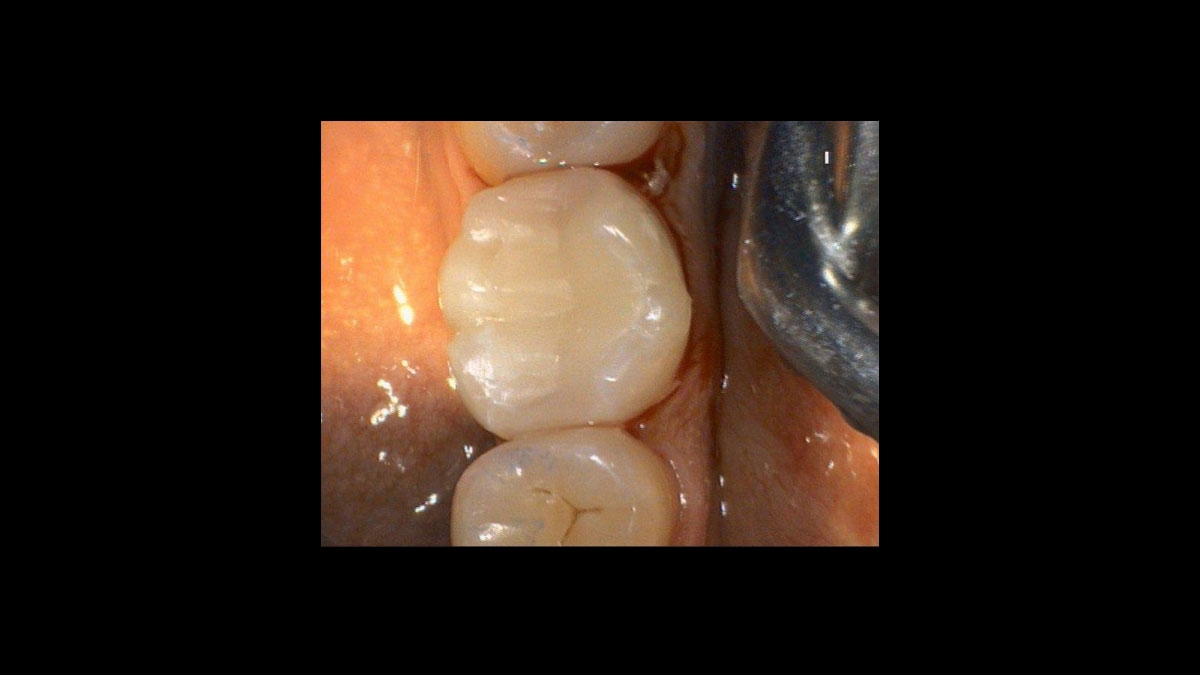

Ceramic Restauration after CEREC treatment